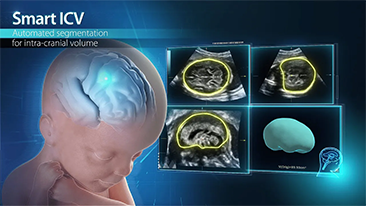

? necessĂĄrio otimizar fluxos de trabalho de obstetrĂcia e ginecologia para suportar grandes volumes na triagem da saĂșde da mulher. Por exemplo, as mĂĄs-forma??es do sistema nervoso central (SNC) s?o uma das anomalias congĂȘnitas mais comuns. Obten??o de imagens ruins devido Ă mĂĄ posi??o fetal, o MSP Ă© particularmente difĂcil de ser encontrado em um ultrassom 2D. Portanto, a detec??o e as medi??es automĂĄticas podem aumentar muito a eficiĂȘncia da realiza??o do exame.